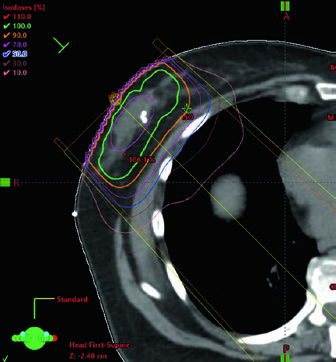

No capítulo, a técnica padrão para radioterapia adjuvante é a radioterapia conformada tridimensional com compensação adequada. Essa compensação pode ser feita com a técnica field-in-field e, quando necessário, com feixes de energia mista, sempre com a meta de manter a dose homogênea no tecido mamário. O mesmo trecho acrescenta um ponto decisivo para a rotina: o mais alto nível de evidência favorece a irradiação de mama inteira em esquema hipofracionado, o que transforma a homogeneidade do plano em requisito central, e não em detalhe periférico.

Essa abertura do capítulo é pragmática. Ela não separa planejamento e delineamento como tarefas independentes, porque a cobertura homogênea da mama depende da forma como o volume é desenhado e da maneira como os tangentes são compensados. Ao citar 3D CRT e IMRT como possibilidades técnicas, o texto não sugere que uma modalidade substitui automaticamente a outra. O recado é outro: qualquer técnica escolhida precisa preservar o mesmo objetivo geométrico e dosimétrico, com cobertura uniforme da mama e controle consciente da dose que alcança coração e pulmões.

As figuras de planejamento deixam esse raciocínio concreto. O exemplo supino mostra tangentes com field-in-field para homogeneidade e um pequeno bloqueio por MLC para proteção cardíaca. Na mesma legenda, a prescrição aparece de forma direta: 42,4 Gy em frações de 2,65 Gy, seguidos de boost com elétrons na cavidade da lumpectomia até 10 Gy em frações de 2,5 Gy. O capítulo, portanto, não trata a compensação como um refinamento opcional. Ela já integra a técnica padrão desde o início do plano.

Quando o boost é indicado, o planejamento mais comum descrito pelos autores usa elétrons em incidência en face. A seleção da energia deve obedecer à profundidade do leito tumoral somada a uma margem, sem ultrapassar a superfície anterior dos músculos peitorais. A figura do boost em posição supina torna isso quase didático ao mostrar a escolha de 12 MeV para garantir cobertura da isodose de 90% até a superfície anterior do peitoral. Se o leito é profundo, o texto admite uma alternativa prática: considerar mini-tangentes.

Coração, pulmões e os detalhes do contorno cardíaco

Em todos os casos, os órgãos de risco devem incluir coração e pulmões. O capítulo especifica que o coração deve ser contornado superiormente até a bifurcação da artéria pulmonar, incluindo o pericárdio e a gordura epicárdica situada entre o músculo cardíaco e o pericárdio. A gordura pericárdica que fica fora do pericárdio não precisa ser incluída. A figura correspondente mostra exatamente essa diferença e evita uma fonte frequente de inconsistência entre planejadores.

Os autores também organizam a hierarquia do que medir. A melhor evidência para proteção cardíaca continua sendo a redução da dose média no coração. Ao mesmo tempo, eles registram que estão surgindo dados que sugerem relevância para a dose recebida pela artéria descendente anterior esquerda e pelo ventrículo esquerdo. Por isso, essas estruturas podem ser contornadas com base nos atlas publicados por Feng et al. e Duane et al., exatamente como indicado nas referências do capítulo.

Essa combinação entre um desfecho consolidado, que é a dose média cardíaca, e uma avaliação mais refinada de LAD e ventrículo esquerdo ajuda a ler o texto sem exageros. O capítulo não troca um parâmetro robusto por outro ainda emergente. Ele propõe que a equipe some precisão quando isso fizer sentido, sem abandonar o indicador com melhor suporte de evidência. Em prática diária, esse equilíbrio combina bem com a recomendação de considerar DIBH nos casos à esquerda e com o uso de pequenos bloqueios por MLC quando o plano supino exigir proteção cardíaca adicional.